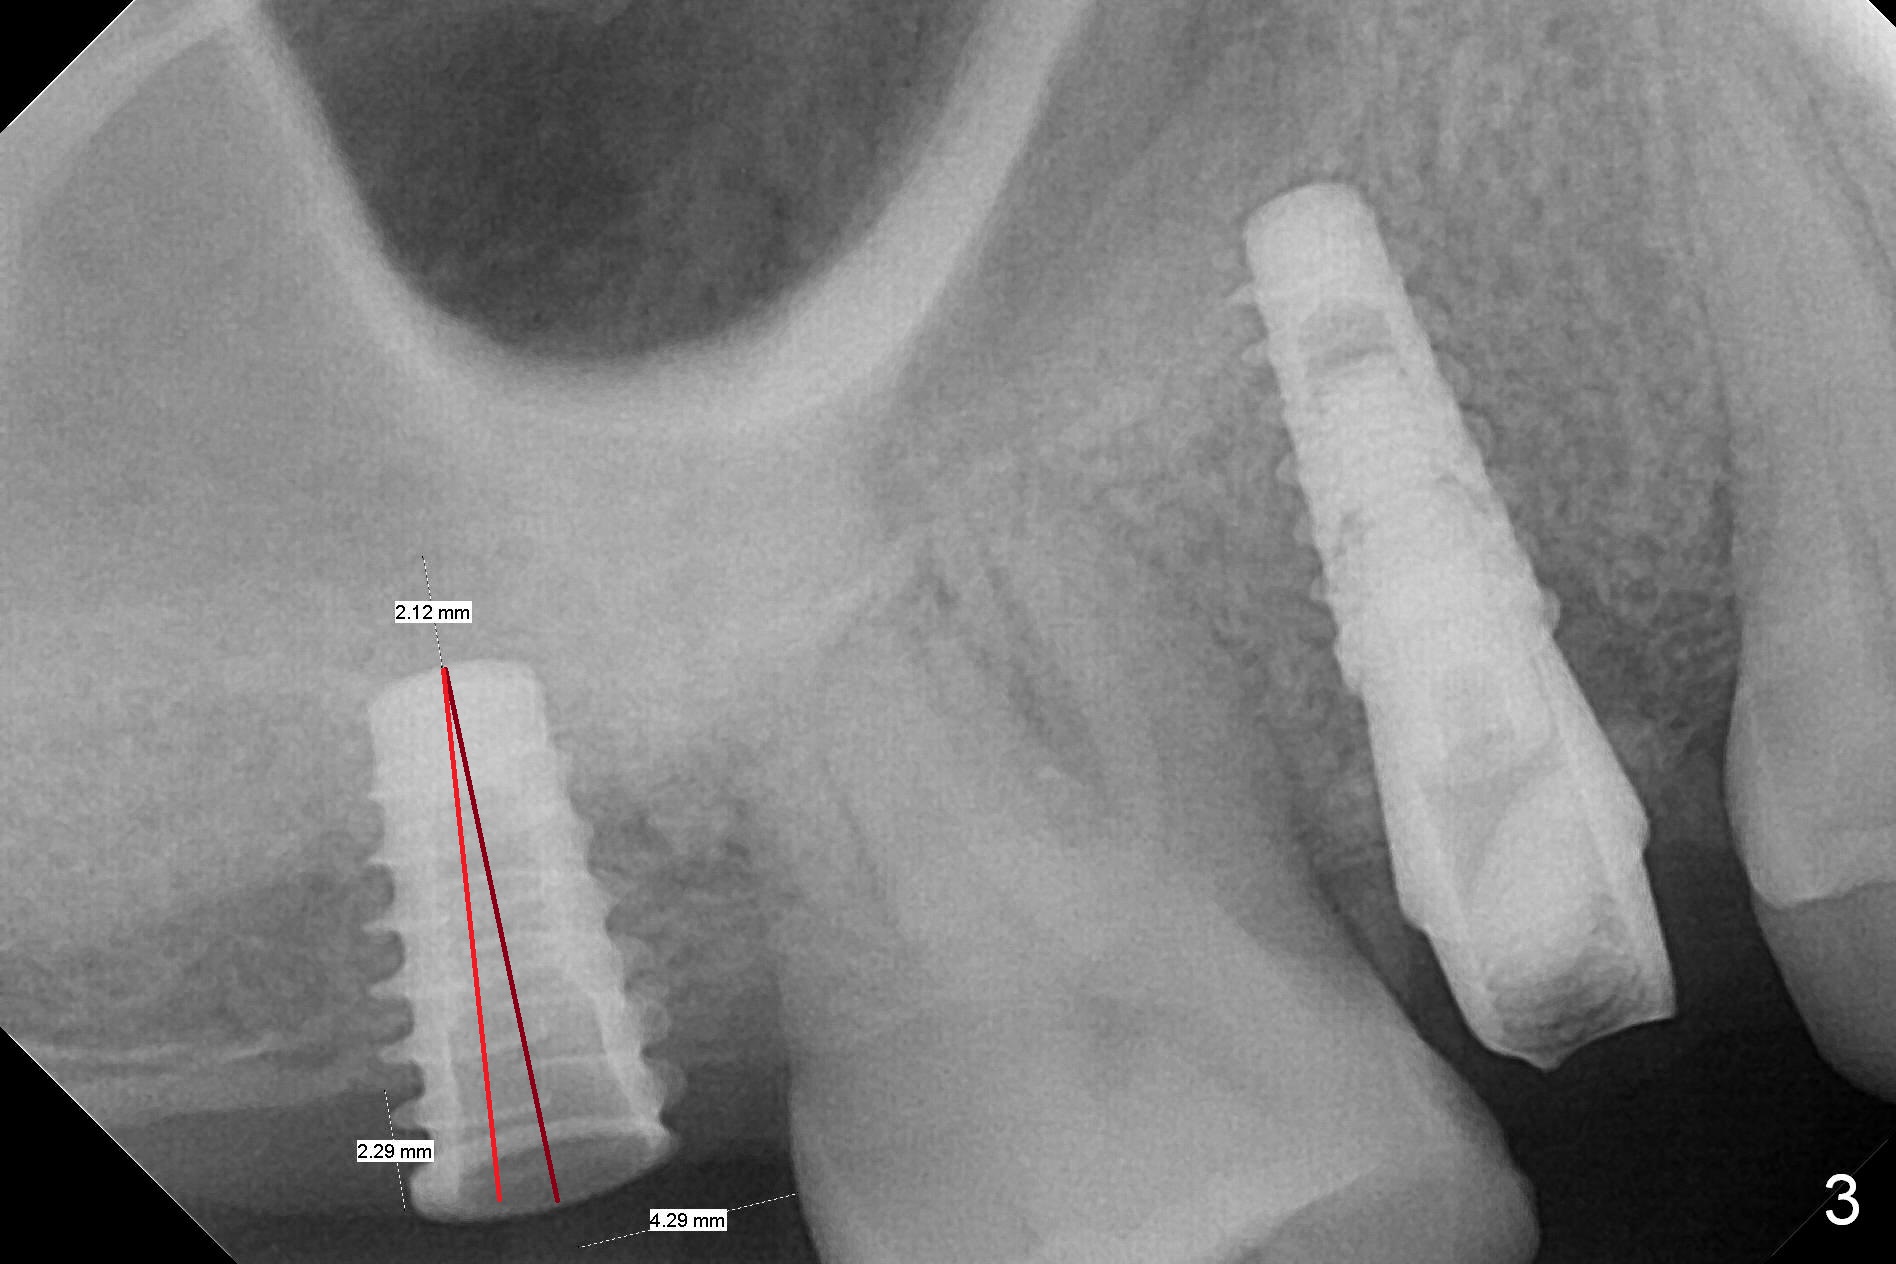

Since the ridge at the site of #2 is wide (Fig.1), Magic Split is used for access and bone density determination. In fact it enters for 9 mm (gingival level), followed by Magic Expander (ME) 3 mm (Fig.2 *). The center of the latter is 3.9 mm from the distal surface of the tooth #3. Lindamann bur is used to move the osteotomy distal, followed by sequential use of MEs until 4.3 mm one. When a 5x9 mm dummy implant is placed, its center is somewhat mesial (Fig.3 brown line). What needs to be done is change the trajectory to the red line so that the coronal end of the definitive implant (5.5x9 mm) will be placed evenly subcrestal (Fig.4,5). It is what happens, although slightly too subcrestal. Insertion torque is <35 Ncm; a 6x4 mm healing abutment is placed. ME 4.8 mm has to be tapped for 13 mm from gingival margin in order to let the implant penetrate the sinus floor. IBS implants seem to lack self tapping ability. Its tap drills should possess this capacity. Allograft/autogenous bone (harvested from dummy implant) is placed prior to implantation. The patient returns for impression 6 months postop (Fig.6,7; #4). A 5x4(3) mm abutment is placed; its height is reduced as well as the opposing supraerupted tooth (Fig.5) prior to impression.